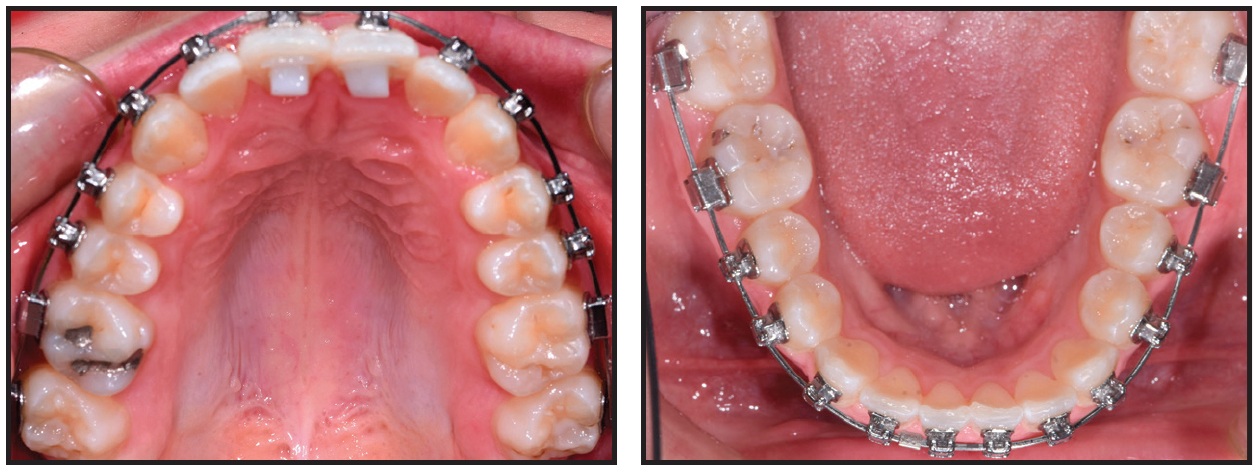

After 10 weeks of treatment, the crowding was resolved, crossbites were corrected, and midlines were coincident, but slight rotations remained (Fig. 11). New .018" × .025" SmartArch Copper NiTi wires were placed in both arches.

After 20 weeks of treatment, the rotations were corrected and proper alignment was achieved (Fig. 12). The bite turbos were removed, and .021" × .025" Insignia custom Copper NiTi archwires were placed for finishing in both arches.

Fig. 10 Case 2. Fixed appliances bonded and .016" SmartArch Copper NiTi wires placed in both arches.

Fig. 11 Case 2. After 10 weeks of treatment, 018" × .025" SmartArch Copper NiTi wires placed in both arches.

Fig. 12 Case 2. After 20 weeks, SmartArch treatment completed, bite turbos removed, and Insignia* treatment started.